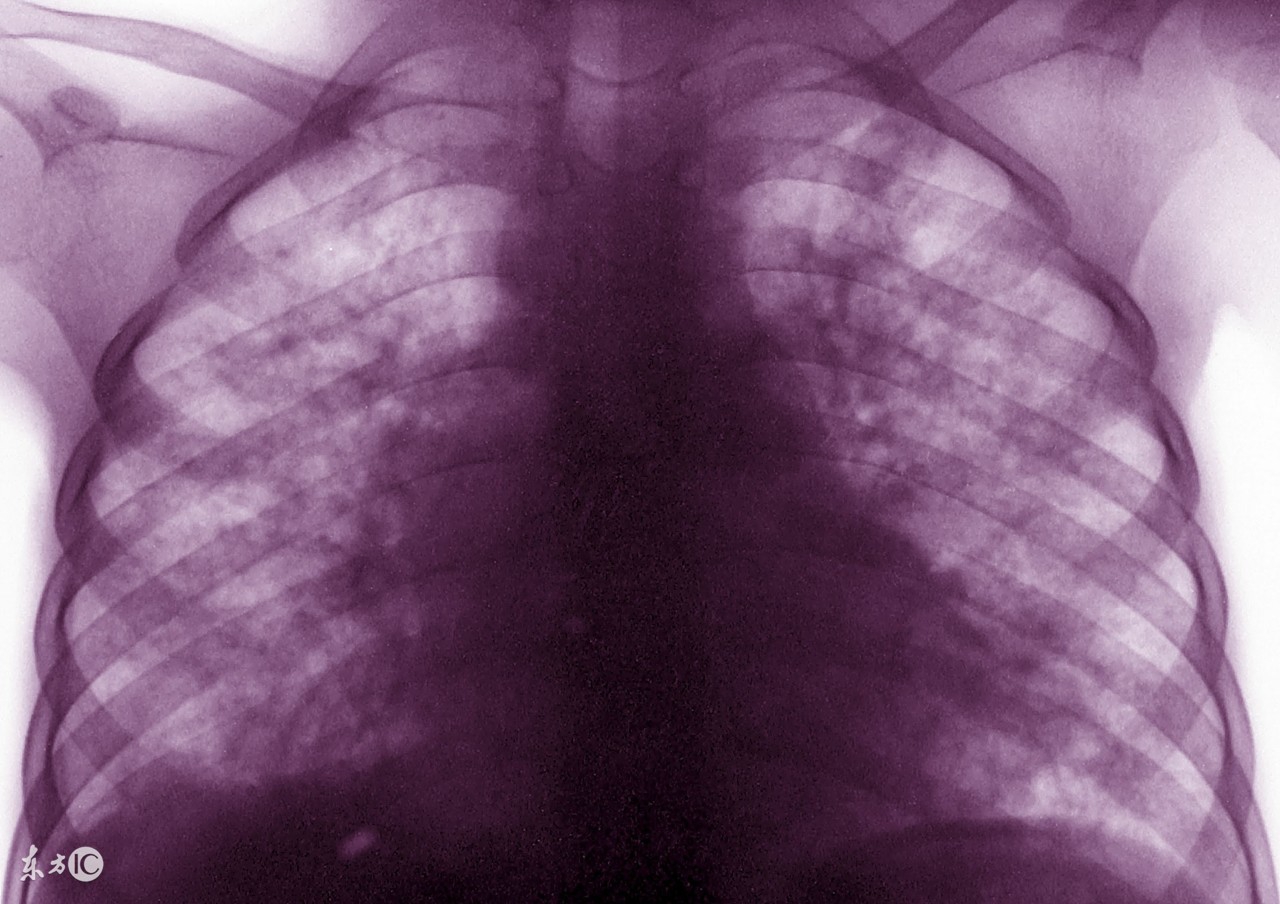

很多肺结核患者在确诊之后,就要马上接受治疗。其实,在临床上,治疗肺结核的方法有很多,很多早期的患者会选择药物治疗,严重的患者就要接受临床治疗了。那么,中医怎样治疗肺结核疾病?其实,治疗方法是根据患者的病情所决定的,中医治疗对于患者的身体损害是很小的。